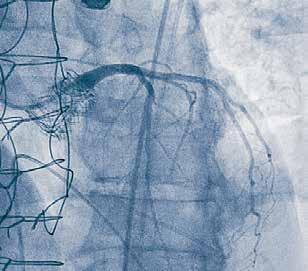

When Doug made it to the cardiac catheterization lab, it was discovered that he had a 100% proximal left anterior descending (LAD) lesion, which was successfully opened with a stent. Falgun Patel, MD, FACC, FSCAI, an interventional cardiologist with Georgia Heart Institute, placed an Impella device in the left ventricle and a Swan-Ganz catheter in the pulmonary artery to manage cardiogenic shock.

BIOMECHANICS OF ATHEROSCLEROSIS

COLLABORATION ON THREE NIH R01 STUDIES

1. Acquire Imaging Data

4. Identify Status

Acquire Undeployed Stent

6. Remove Stent from Lumen 5. Deform undeployed stent

3. Contour Lumen

7. Compute WSS